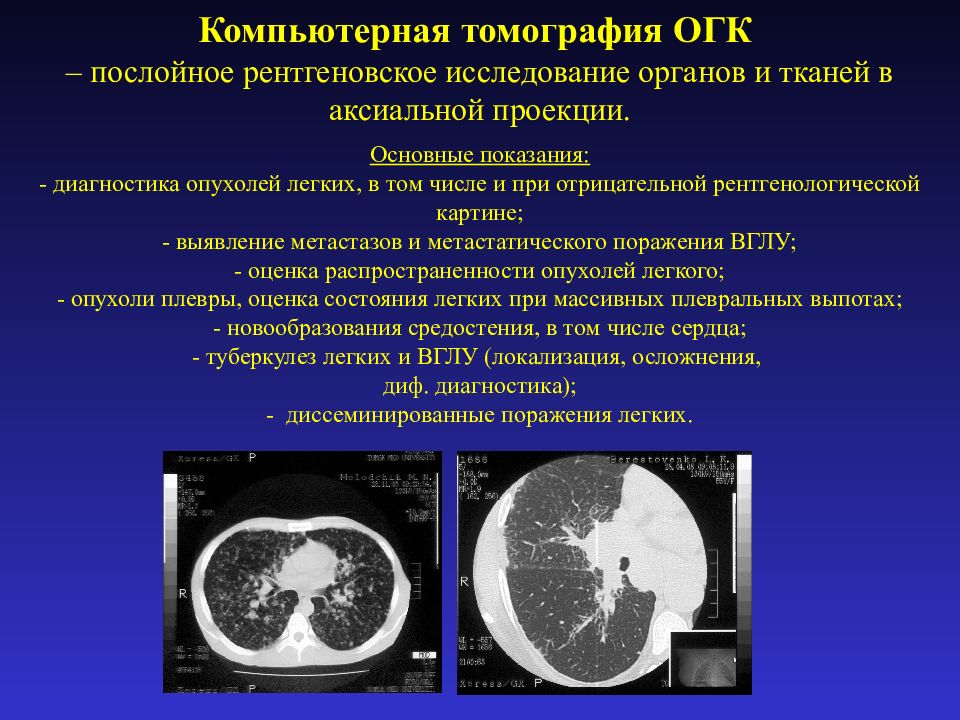

Рентгенологические изображения и синдромы патологии легких

Раздел: Кадры-подсказки